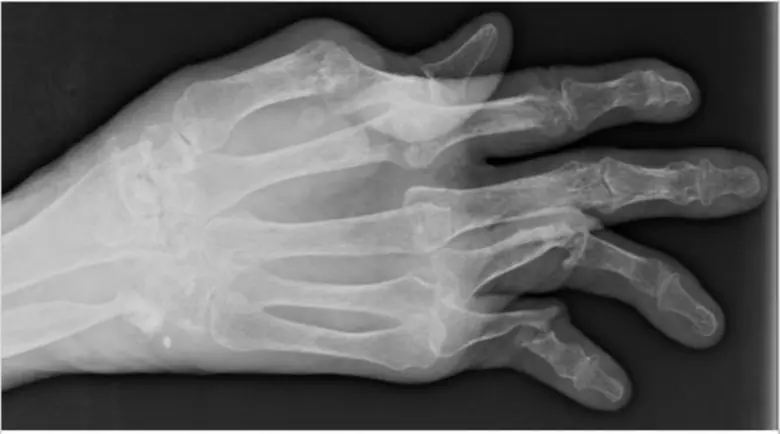

การอยู่กับโรคที่สามารถมองเห็นได้ชัดเจนอาจสร้างความเจ็บปวดอย่างมาก คุณรีนา รูพาเรเลีย (Reena Ruparelia) จากประเทศแคนาดา เปิดเผยประสบการณ์ว่า "ฉันเกิดอาการปะทุรุนแรงช่วงปลายปี 2558 มือและเท้าของฉันเต็มไปด้วยผื่นและรอยแตก ฉันต้องใช้พลาสติกแรปและถุงมือเพื่อรักษาความชุ่มชื้น วันหนึ่งฉันถอดออกตอนอยู่ที่ทำงาน จ้องดูมือของตัวเอง และเริ่มตื่นตระหนก ฉันแทบไม่เชื่อสายตาเลยว่ามันแย่ขนาดนี้ ฉันตัดสินใจนั่งแท็กซี่กลับบ้านและลางานสามเดือนด้วยเหตุผลด้านความทุพพลภาพ"

"โรคสะเก็ดเงิน" เป็นโรคเรื้อรังที่ยังไม่ท... เตือนผู้ป่วยโรคสะเก็ดเงิน ระวังเสี่ยงข้ออักเสบสะเก็ดเงิน..อันตรายถึงพิการ — "โรคสะเก็ดเงิน" เป็นโรคเรื้อรังที่ยังไม่ทราบสาเหตุที่แน่ชัด แต่มักเกิดจากความผ...